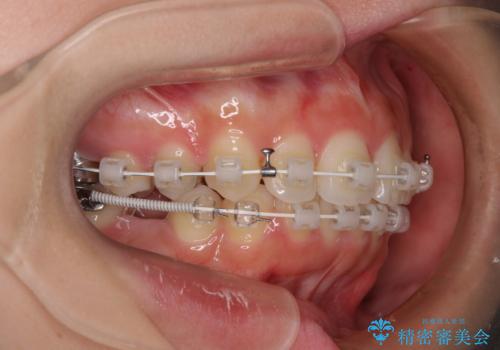

- 矯正装置

- 審美装置

上顎前歯の突出感は、上顎全体が前方に位置していることが原因であったため、補助装置により上顎全体を後方に移動させることとしました。

後方移動と同時上下歯列をワイヤー装置にて整え、奥歯の欠損部には矯正治療の途中でインプランを埋入していくこととしました。